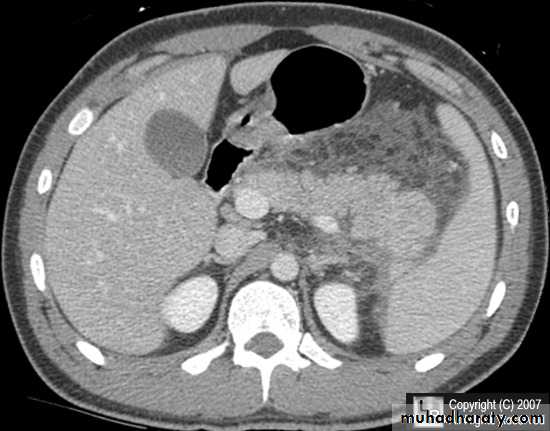

CT abdomen

Hydatid cyst

Appear as large oval hypo dense area density of fluid with well defined margin , sometime at their periphery multiple flecks of calcification are seen at their periphery .

Hydatid cyst with daughter cyst , appear as multiple hypo densities rounded area within the main loculi with multiple rim of

calcification

Secondary metastasis in the liver

Multiple rounded hypo density areas of different density , shape & different size .

Pattern of enhancement is either uniform , target or bulls eye pattern .

Hepato megaly .

Hydatid cyst within the liver

Secondary metastasis within the liver